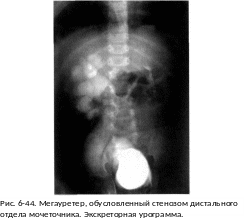

6.3.12. Мегауретер

Мегауретер (мегадолихоуретер, гидроуретер, уретерогидронефроз) — значительное расширение мочеточника и коллекторной системы почки, вызванное механической обструкцией пузырно-мочеточникового

сегмента, пузырно-мочеточниковым рефлюксом или недоразвитием стенок мочеточника.

Нерефлюксирующий мегауретер развивается на фоне патологии мочеточника в дистальном отделе (диспластические изменения в мышечном слое, стеноз во внутрипузырном сегменте мочеточника и др.). Нарушение опорожнения мочеточника приводит к его значительному расширению и извитости (мегадолихоуретер; рис. 6-43), дилата-ции коллекторной системы почки (рис. 6-44), быстрому возникновению пиелонефрита.

На экскреторных урограммах отмечают запаздывание выделения почками контрастного вещества, деформацию коллекторной системы, расширение и извитость мочеточников. Эвакуация контрастного вещества из них замедлена.